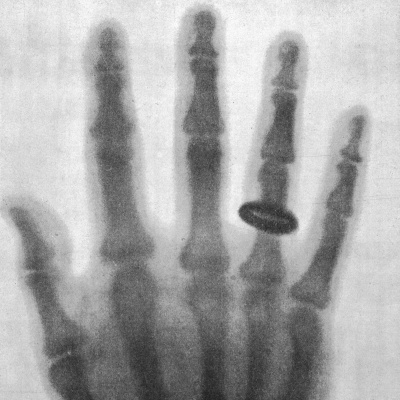

1895 entdeckte der Physiker Wilhelm Conrad Röntgen spezielle Strahlen, die unterschiedlichste Materialien durchdringen. Kurz darauf erlangte das Röntgenbild von der Hand seiner Gattin Berühmtheit. Seitdem wurde die Technik immer weiter entwickelt. (BR 2015) Autorin: Anne Kleinknecht